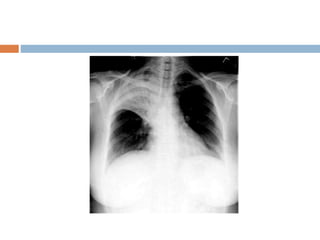

Massive pleural effusion

 Opacification of entire hemithorax and shifting

of mediastinum to opposite side

 If the effusion crosses 2nd rib anterior border it

is said to be massive

 If it crosses 4th rib it is said to be moderate

 Below 4th rib is mild

White out lung